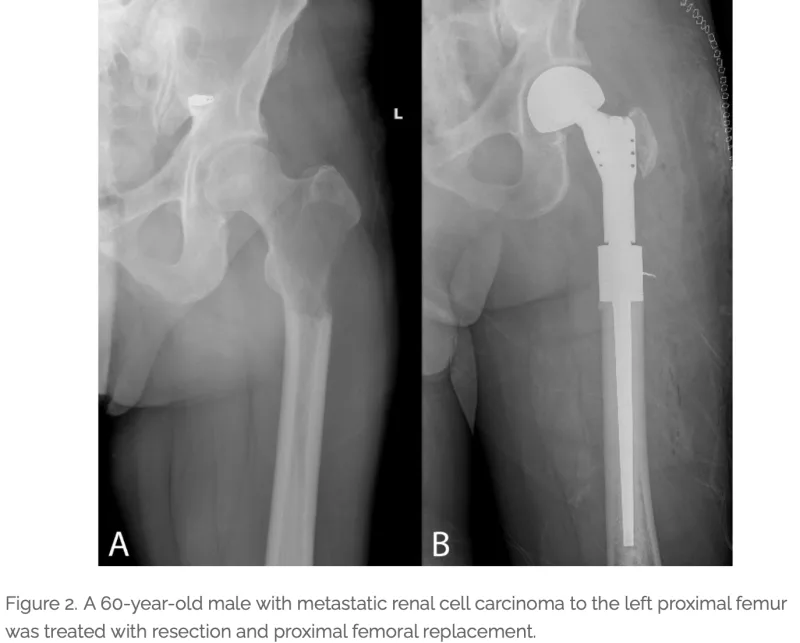

腎癌の大腿骨転移による切迫骨折の症例で, 先月当科を初診された方です.

当時は骨折寸前の状態だったため, 大学病院に紹介し, 腫瘍切除+腫瘍再建用人工骨頭挿入術が行われました.

幸い骨折には至らず, 現在は杖歩行が可能な状態にまで回復されています.